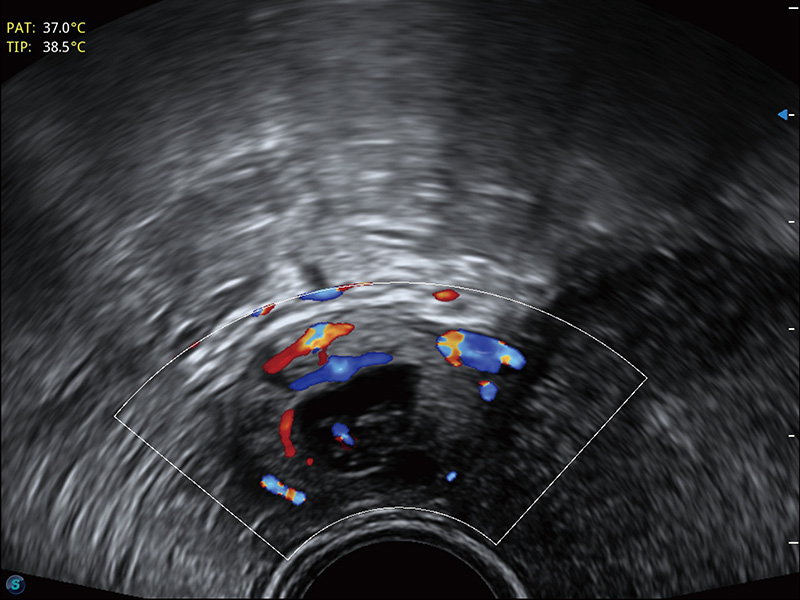

超声引导下双侧卵巢穿刺取卵

宫外孕血流

输卵管间质部妊娠